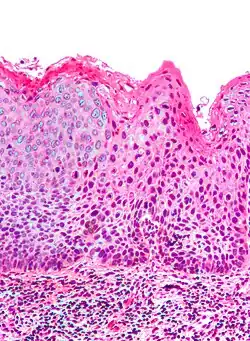

| Micrograph of (classic) vulvar intraepithelial neoplasia III. H&E stain. | |

Medically speaking, the term denotes a squamous intraepithelial lesion of the vulva that shows dysplasia with varying degrees of atypia. The epithelial basement membrane is intact and the lesion is thus not invasive but has invasive potential.

Classic vulvar intraepithelial neoplasia: associated with developing into the warty and basaloid type carcinoma. This is associated with carcinogenic genotypes of HPV and/or HPV persistence factors such as cigarette smoking or immunocompromised states.